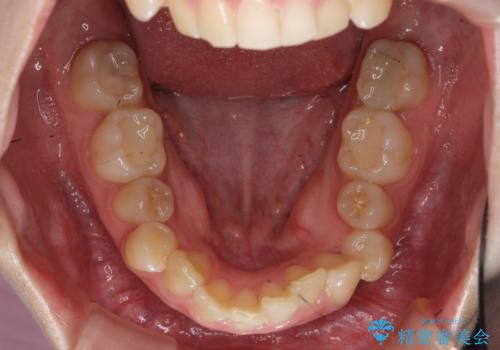

- 前歯の並びと下の歯のがたつきを主訴に来院。

左下にがたつきが集中していました。

左下の第一小臼歯が歯列からはみ出て、近心傾斜しており、抜歯の上ワイヤー矯正の選択肢もお話ししましたが、非抜歯で、インビザライン矯正を希望されました。左下の第一小臼歯は完全に並べることは難しいと初めから説明し、納得いただいた上で治療開始しました。